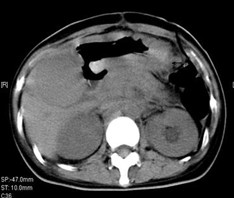

女,40岁,2006年10月底确诊为胃腺癌(皮革胃),腹腔淋巴结转移;2006年11月外科手术时见腹腔广泛转移(粘连),病灶无法切除(下图1a,b),预期生存期低于3个月;留置(胃)造瘘管。2006年12月开始今又生联合化疗治疗,今又生2×1012VP,室温下自行融化后加入到100ml生理盐水中,30~40分钟内静脉滴注完毕,1/次/周,连续使用6周。今又生给药三天后静脉化疗。2007年7月外科手术拔除造瘘管;2007年9月随访,患者状况良好,无复发。

1a 治疗前胰腺体部和主动脉前方淋巴结较多较大,胃底和体部较厚僵硬

1b治疗后 淋巴结较少并缩小,胰腺和主动脉之间脂肪间隙恢复清晰,胃底和体部较前变薄,柔软

2a 治疗前 主动脉前方,胃底和脾门之间见大量结节状淋巴结

2b 治疗后 主动脉前方,胃底和脾门之间淋巴结大部分消失缩小,脂肪间隙较前清晰